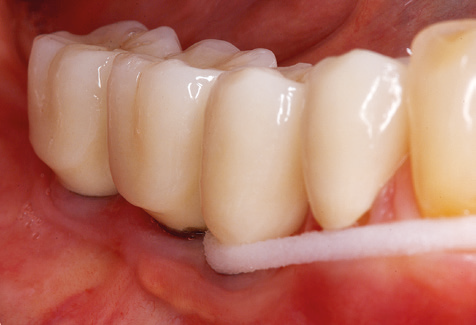

Dopo la pulizia meccanica delle superfici dei denti e degli impianti, le superfici dei denti naturali vengono pulite manualmente utilizzando strumenti manuali standard. Quando si esegue la pulizia manuale, è necessario prestare particolare attenzione a mantenere il corretto angolo di applicazione, un'adeguata nitidezza, un buon supporto e lavorare con la curette dall'apicale al coronale. Curette in titanio o carbonio devono essere utilizzate per la post-pulizia delle strutture dell'impianto (Fig. 8). Oltre all'uso di dispositivi ad ultrasuoni, i dispositivi power jet possono essere utilizzati anche in odontoiatria conservativa. Tuttavia, si deve considerare che queste procedure non sono adatte per rimuovere depositi duri e quindi non possono sostituire completamente l'uso di strumenti manuali e strumenti ad ultrasuoni. In tutti i casi, la pulizia è seguita dalla lucidatura meccanica del dente accessibile e delle superfici dell'impianto con ventose e composti di lucidatura (Fig. 9).